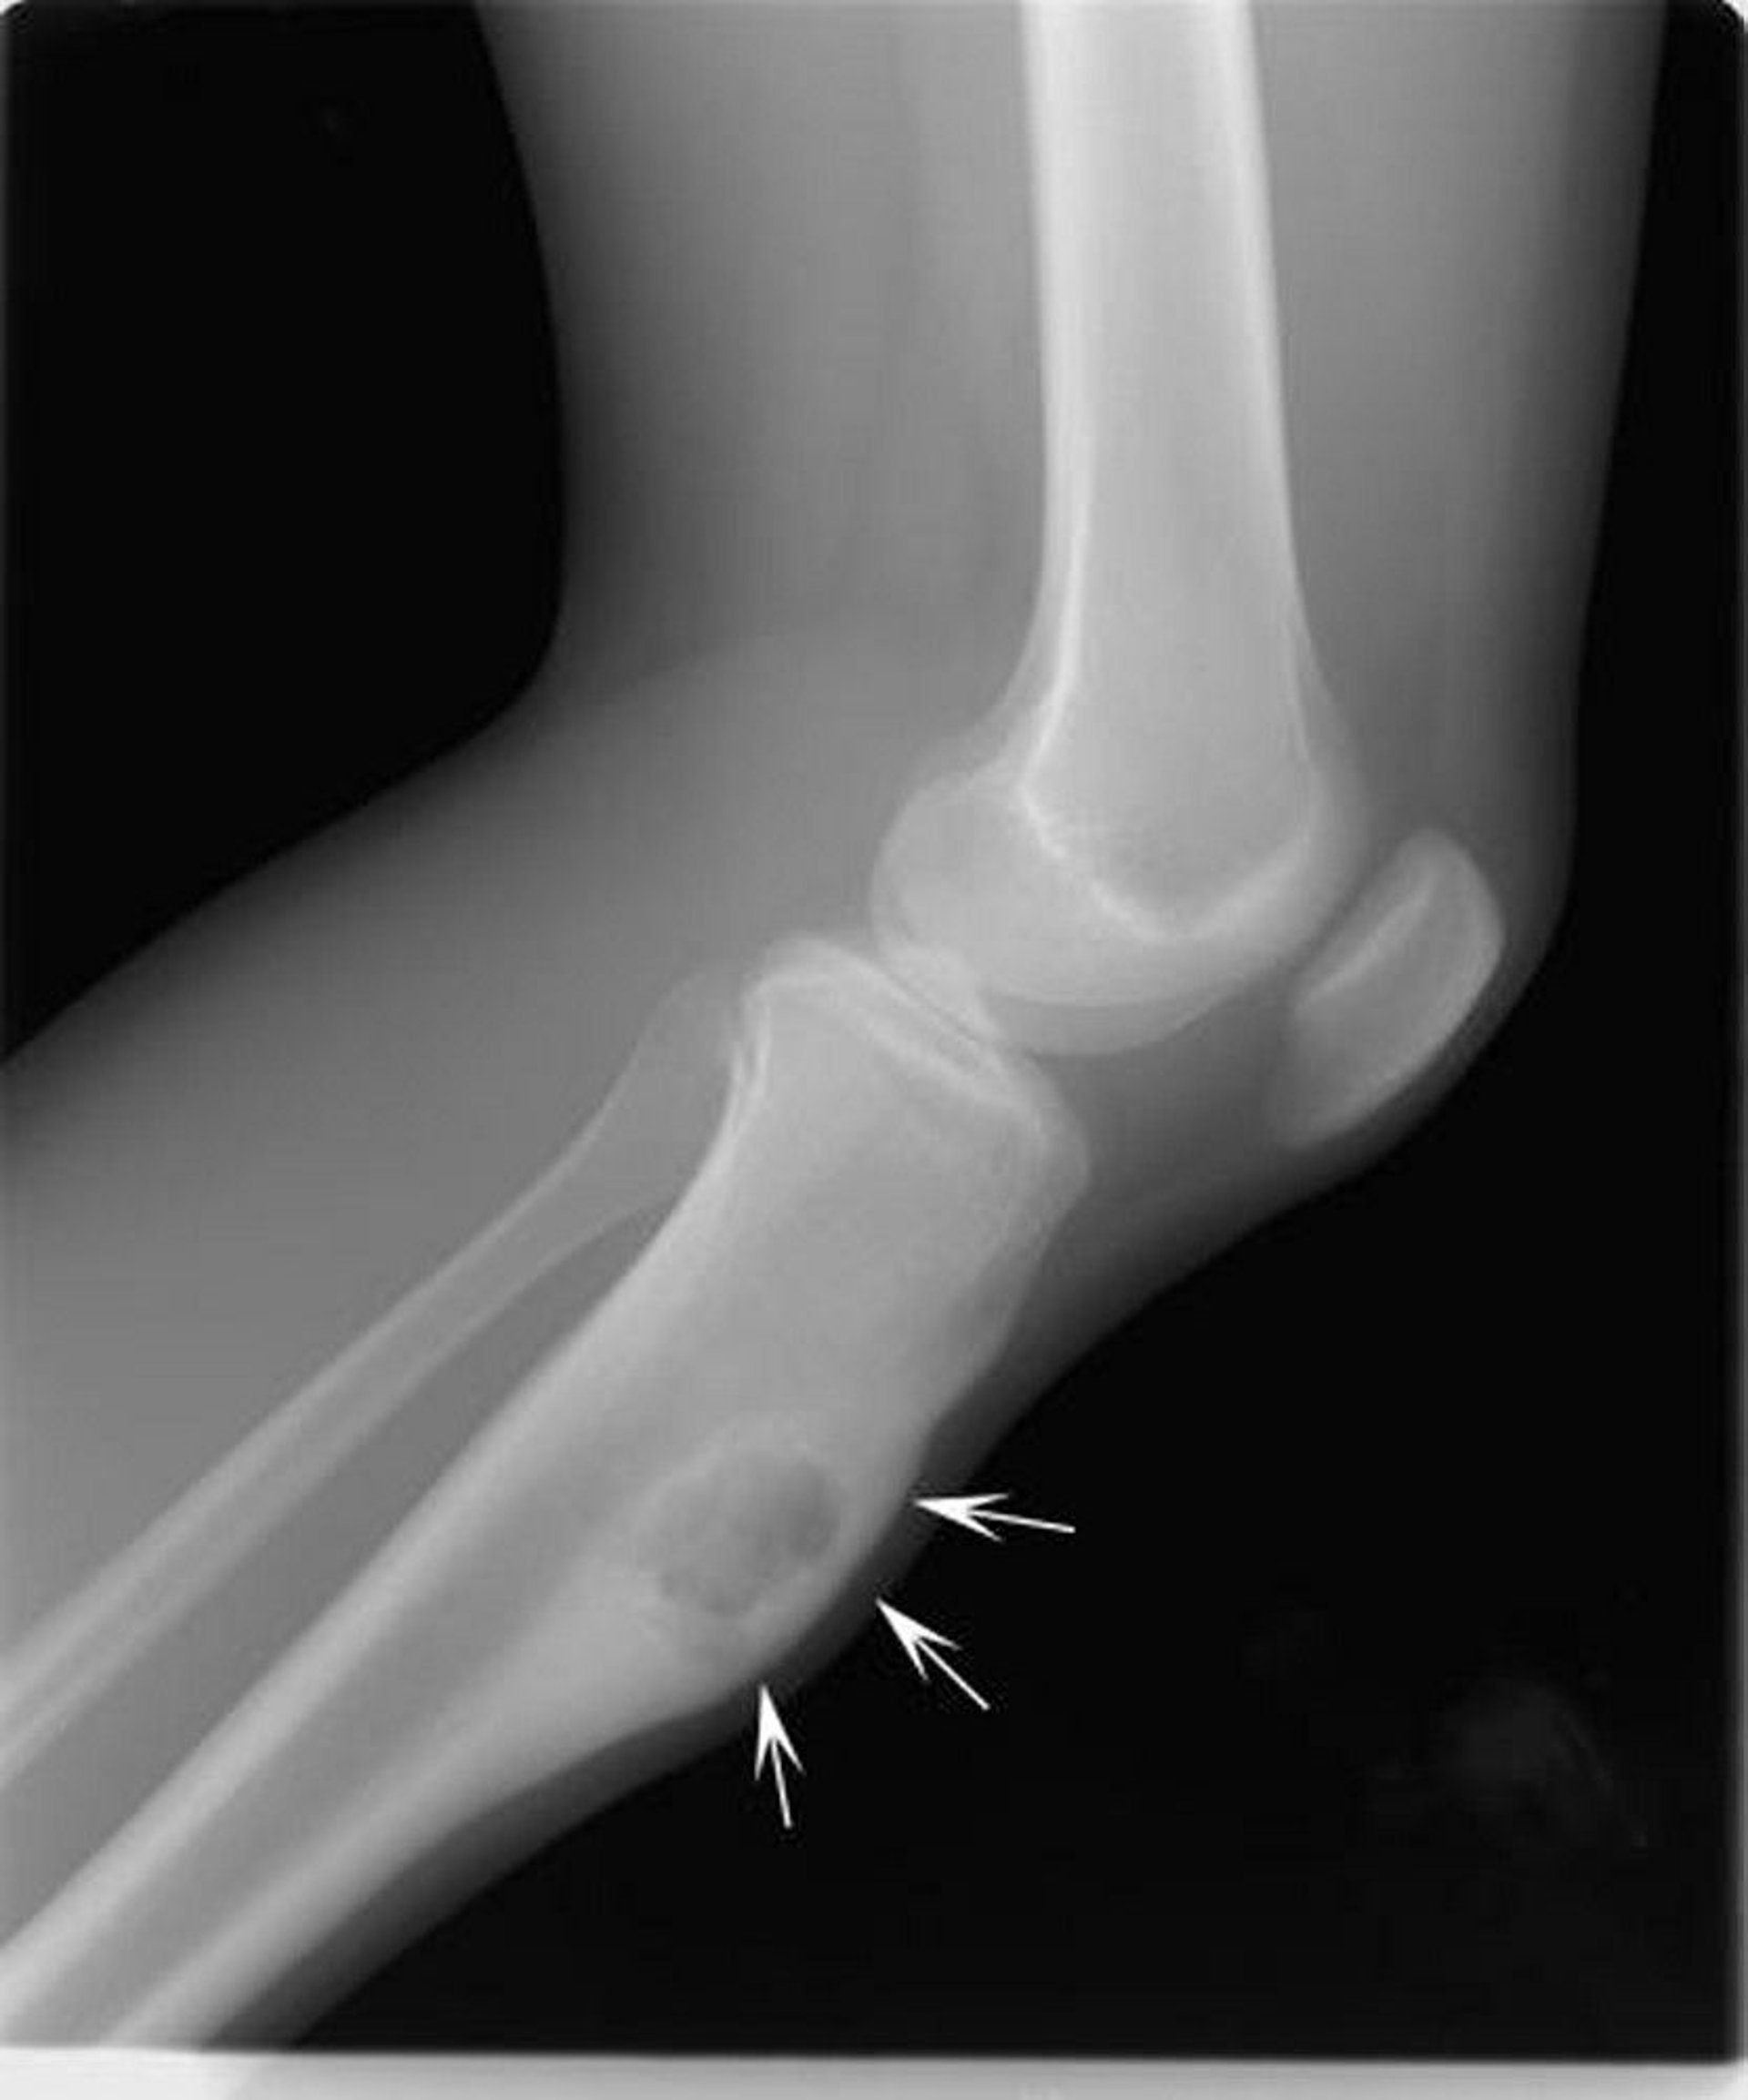

This radiograph of the knee shows a chondromyxoid fibroma in the tibia below the knee (arrows), expanding the bone in the front.

Image courtesy of Michael J. Joyce, MD, and Hakan Ilaslan, MD.